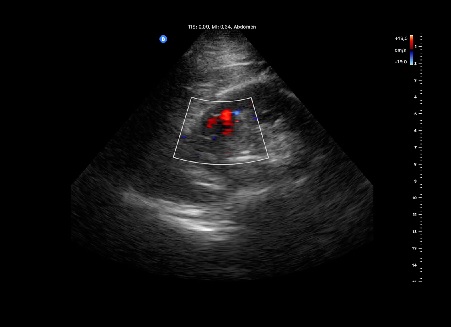

Se realiza con sonda ecográfica portátil. Se inicia el estudio ecográfico del abdomen a nivel de la línea axilar media derecha, donde realizamos cortes longitudinales y transversales. En el riñón derecho se observa, a nivel del polo superior, una lesión sólida heteroecoica, hipoecogénica respecto al parénquima circundante, redondeada, de bordes bien definidos, sin refuerzo posterior (figura 1), de 4,10 x 4,56 cm (figura 2) y con vascularización (Doppler positivo) (figura 3).